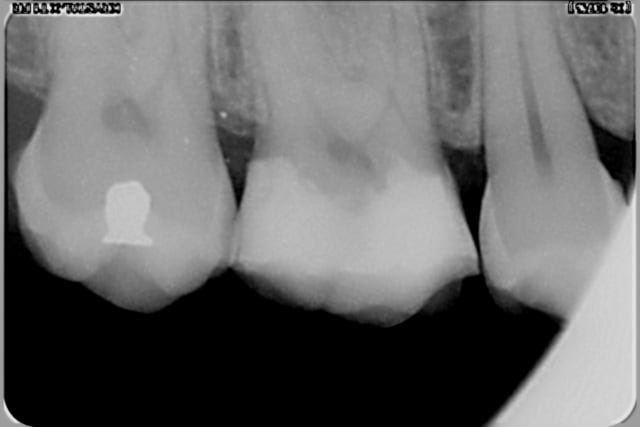

et deux exemples en radios de cas similaires, un peu plus sous gingivaux d'ailleurs

T'as pas oublier un truc au distal de la 5 ? Sur la radio on dirait une carie...

je sais, c'est pour ça que j'ai refait le composite mésial sur la 6, vérifier si il y avait ou pas une carie distale sur la 5